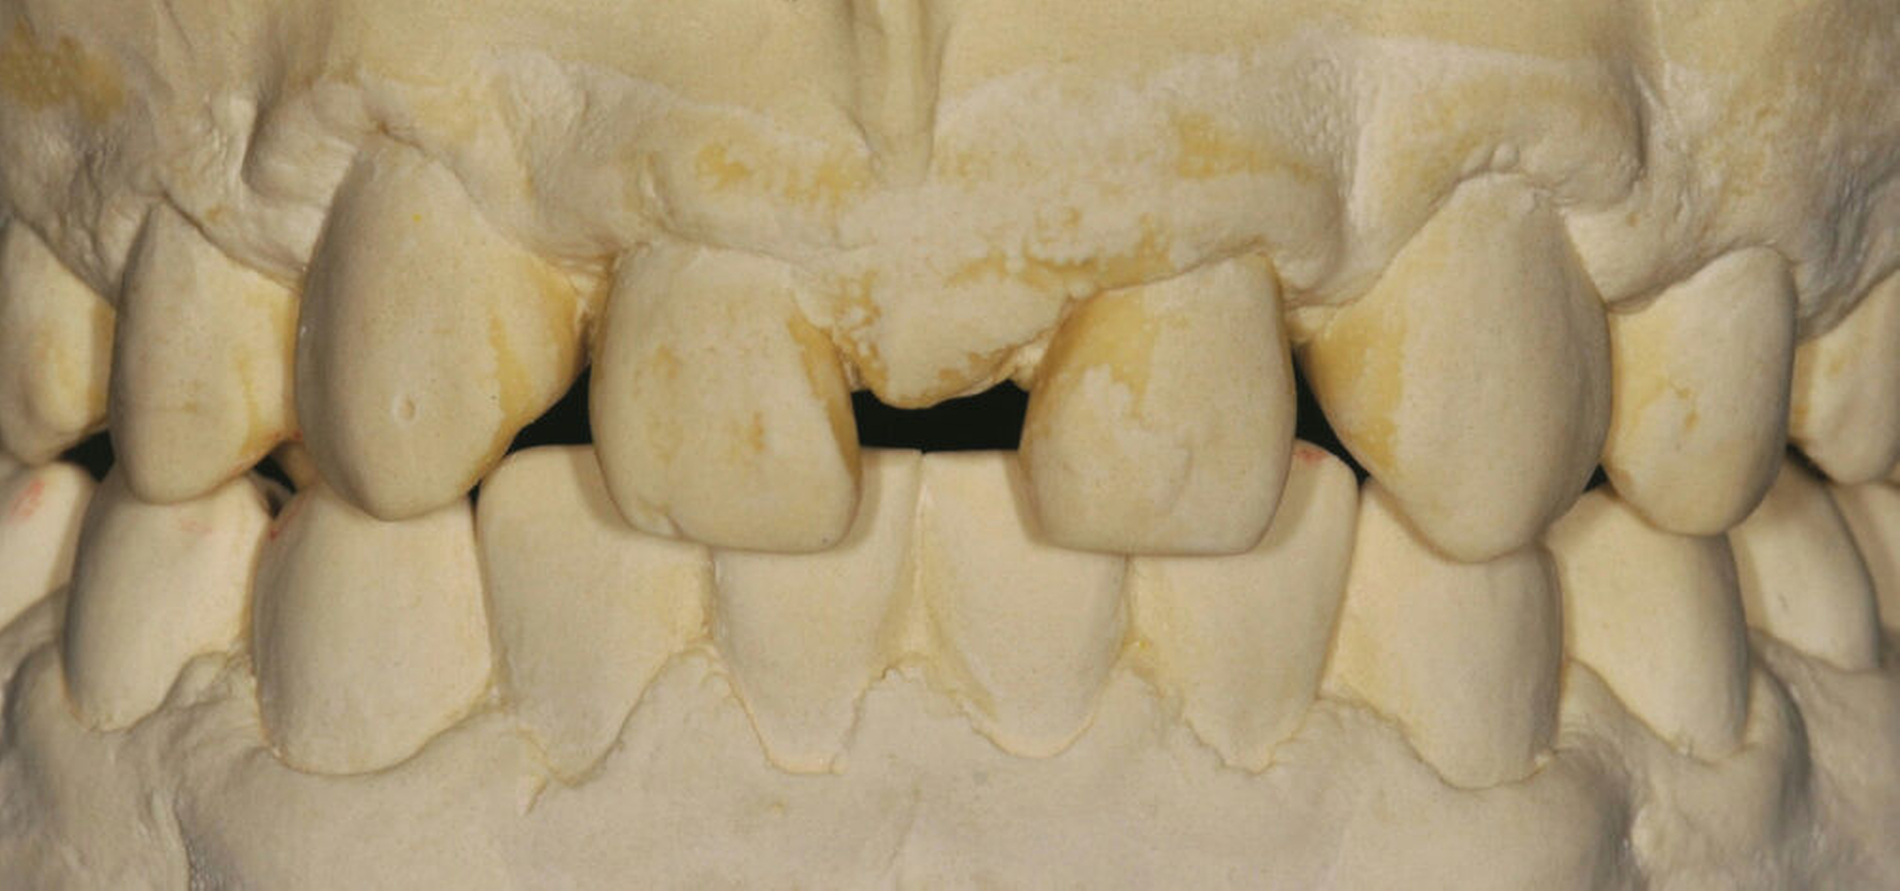

Zur Planung und Simulation des restaurativen Lückenschlusses mithilfe eines Wax-ups werden zunächst Situationsmodelle des Ober- und des Unterkiefers angefertigt.